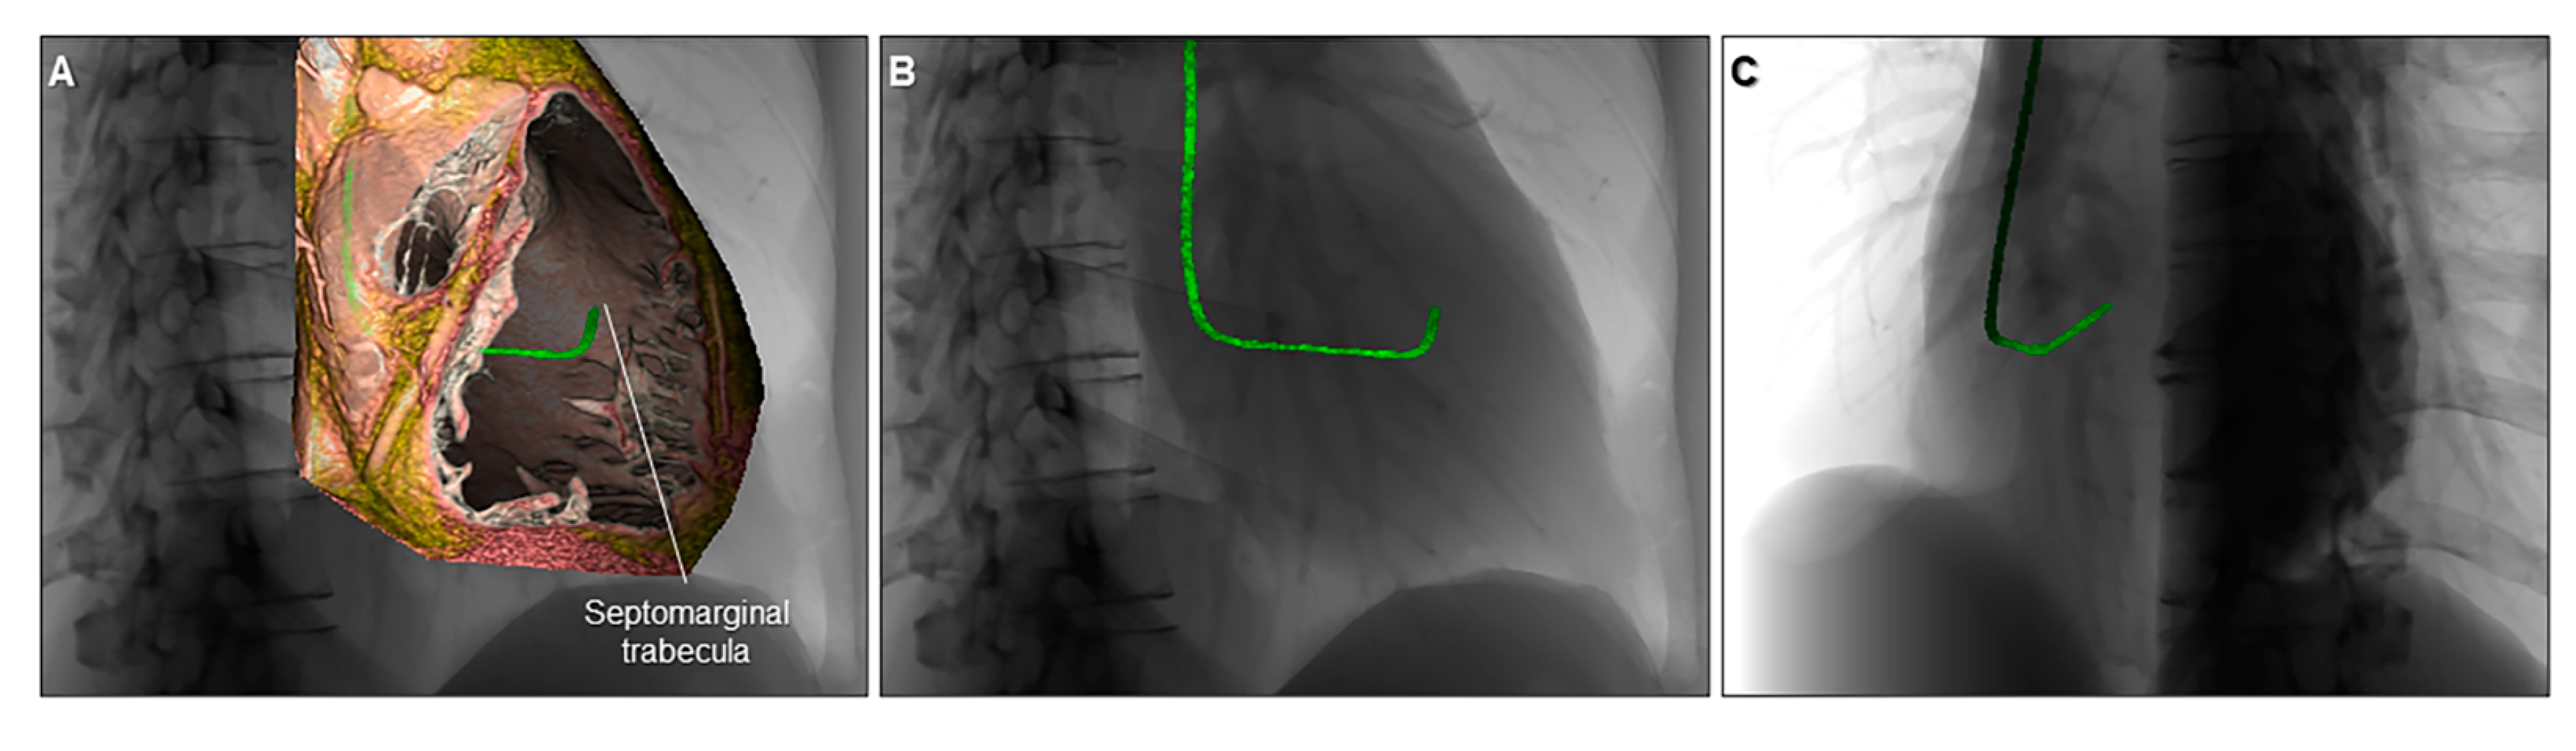

7. Advanced Application of the Three-Dimensional Imaging